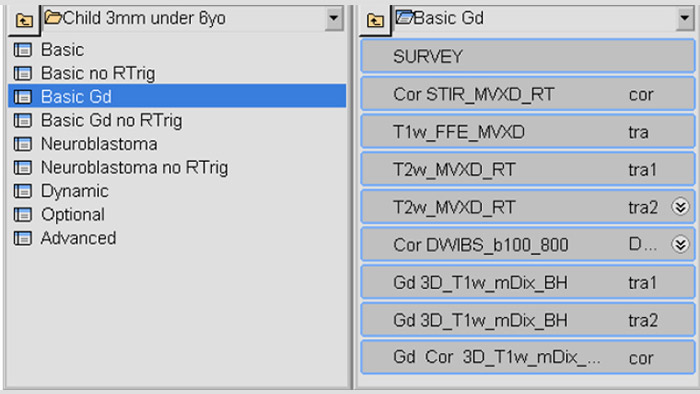

Dedicated pediatric oncology ExamCards

An extensive set of dedicated pediatric ExamCards was developed in a collaboration with some expert users in Germany and based on the guideline from the European Society for Pediatric Oncology Brain Tumor Imaging Group (Nov 2017) and consensus of 11 German Philips MRI users (March 2019). Some highlights are:

Neuro-oncology ExamCards for 3.0T

Body-oncology ExamCards for 1.5T

Examples of 3.0T neuro-oncology ExamCards (left) and 1.5T body-oncology ExamCards (right) for a selected age group. The list of sequences from the highlighted ExamCard is shown on the right. These ExamCards are part of the Philips DACH Pediatric Reference Scan Protocols